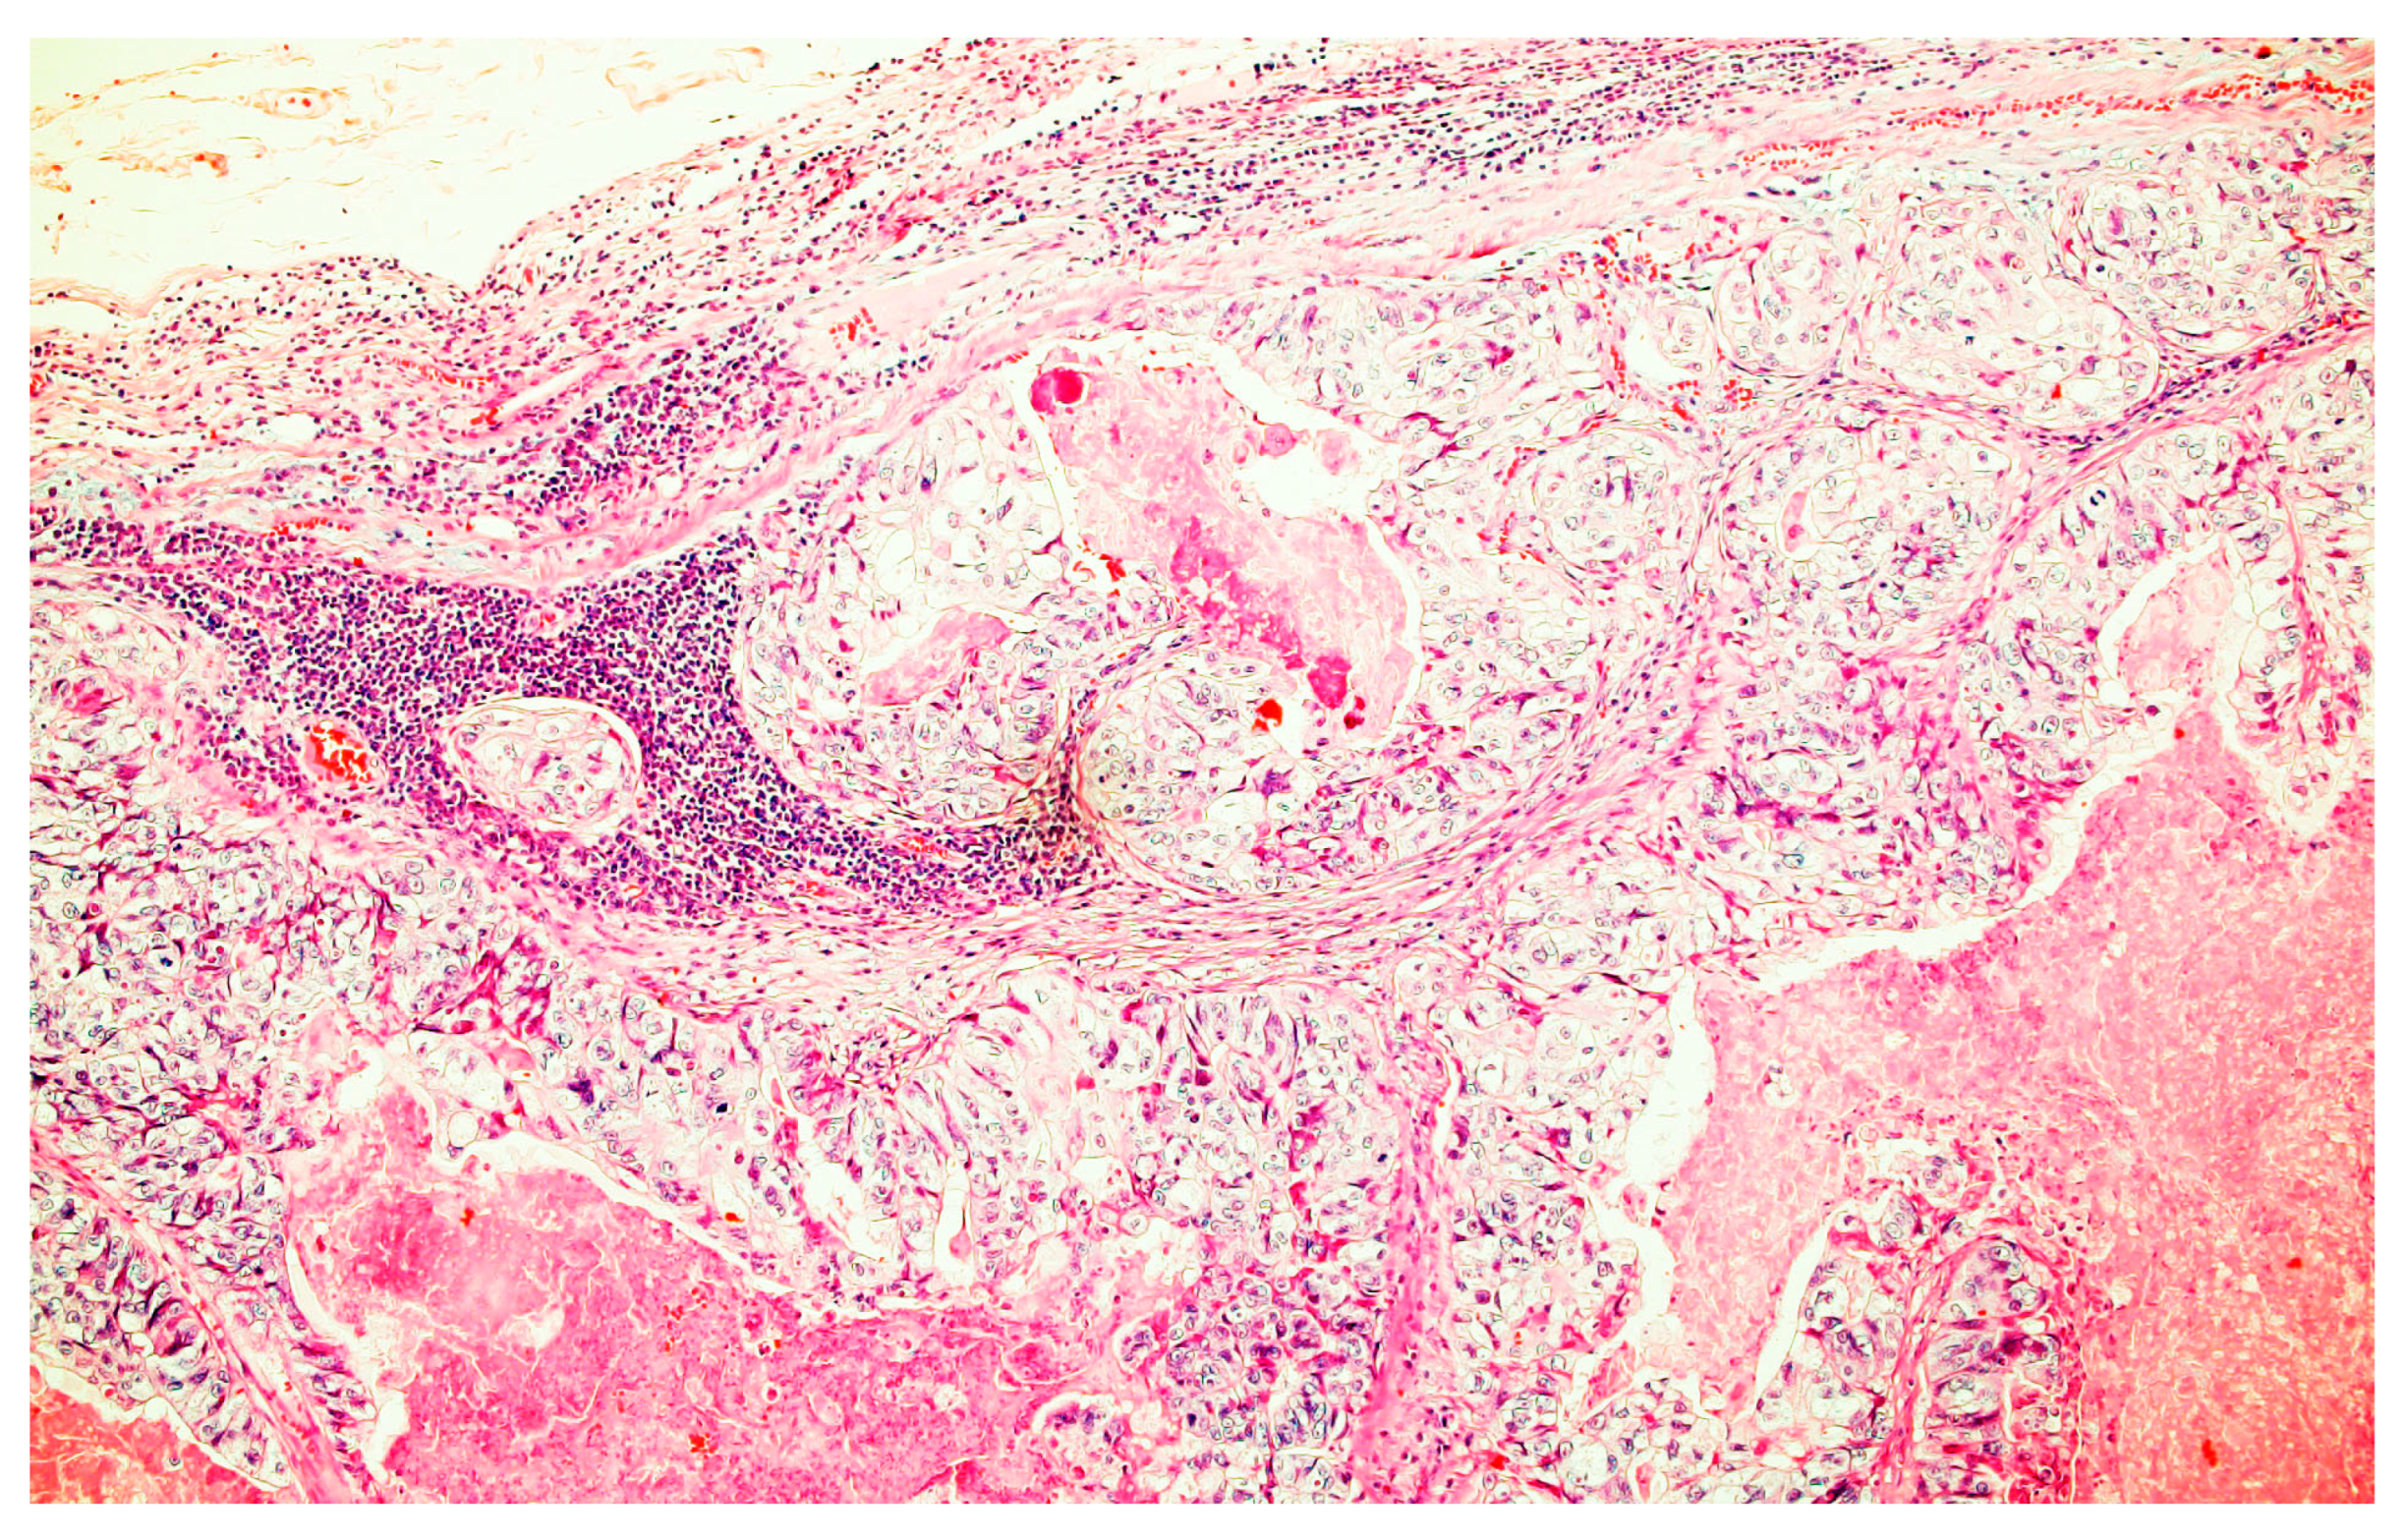

2.1. Case Report